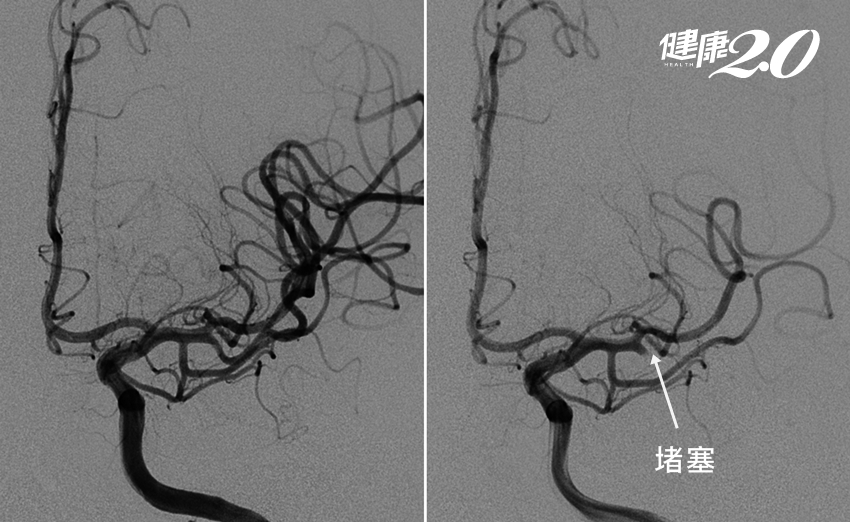

家人覺得奇怪,送他到醫院,一開始以為是精神失常,但做了磁振造影檢查(MRI)後,才發現他的左側的中大腦動脈的分枝血管堵塞,造成左側界於次頂葉及顳葉之間的「語言感覺區」壞死。

幸好這個病人在送來的時候,還在黃金時間內,就直接進行取栓,將堵在血管上的血栓取出,病人也逐漸復原。